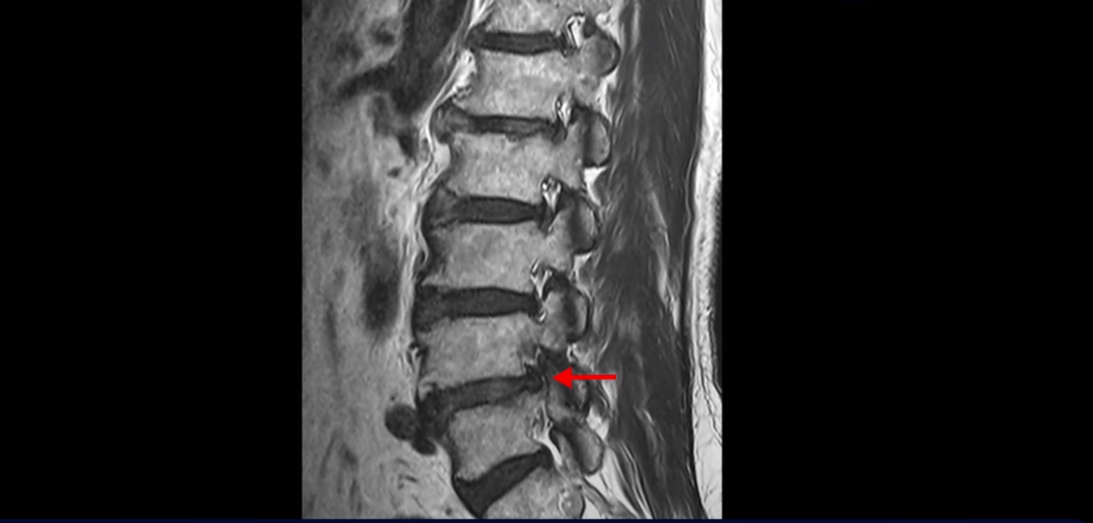

먼저 이분 MRI를 보면서 간단히 설명드린 후 어떻게 신경이 눌려서 반드시 수술해야 한다는 환자나 이 환자분처럼 수술이 필요하지만 나이가 많아서 못한다고 하는 환자분을 수술 없이 치료할 수 있는지 또 치료는 어떻게 하는지 자세히 설명드리겠습니다.

이분 MRI를 보면 척추의 여러 마디가 퇴행이 진행되어 안 좋습니다.

특히 4번 5번 마디가 제일 안 좋은데 보시다시피, 하얗게 보여야 될 신경이 거의 안 보일 정도로 척추관이 좁아져 있습니다.

이분은 허리도 아프지만 왼쪽 엉덩이와 다리가 너무 심하게 저리고 아팠는데 역시나 왼쪽 신경 가지가 빠져나가는 구멍이 막혀 있어서 매우 어둡게 보입니다.

이분은 다리가 너무 아파 걷기 어려워 지팡이를 짚고 모커리에 내원하셨는데요. 어떻게 이런 환자분들을 수술 없이 치료해서 잘 걷게 만들고 심지어는 지팡이 없이 걷게 만들 수 있을까요? 또 어떻게 굽어진 허리가 펴질까요? 지금부터 설명해드립니다.